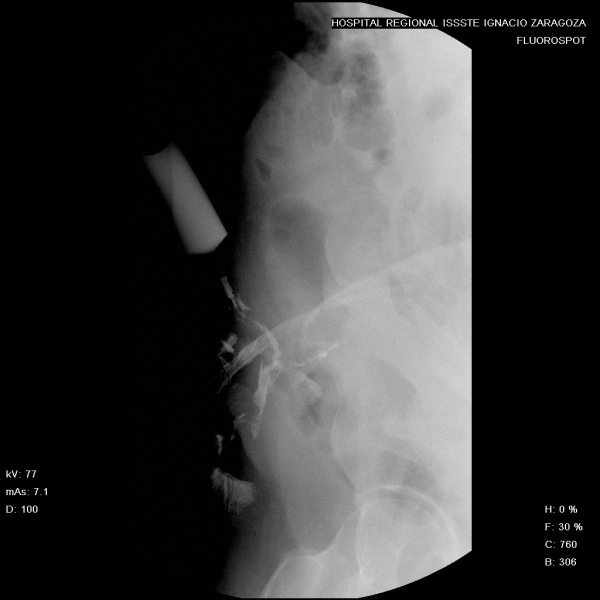

Sinografia o fistulografia de pared abdominal. 877400 Idime

IDIME. Instituto de Diagnóstico Médico. Código de Convenio : 8915

BOGOTÁ

Sede Norte: Autopista Norte No. 122 – 68

BUCARAMANGA

Carrera 27 No. 30 - 15 Segundo Piso Hospital Universitario Los Comuneros

INCLUYE MEDIO DE CONTRASTE